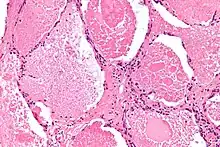

| Micrograph of pulmonary alveolar proteinosis, showing the characteristic airspace filling with focally dense globs referred to as chatter or dense bodies. H&E stain. | |

Lung washings or tissue for histopathologic analysis are most commonly obtained using bronchoalveolar lavage and/or lung biopsy.[13] Characteristic biopsy findings show filling of the alveoli (and sometimes terminal bronchioles) with an amorphous eosinophilic material, which stains strongly positive on PAS stain and the PAS diastase stain. The surrounding alveoli and pulmonary interstitium remain relatively normal.[14] Electron microscopy of the sample, although not typically performed due to impracticality, shows lamellated bodies representing surfactant.[15] An alternative diagnosis with similar histomorphologic findings is Pneumocystis jirovicii pneumonia.[15]

Lung washings characteristically yield a fluid which is "milky"composition. Under the microscope, samples show 20-50 micrometer PAS-positive globules on a background of finely granular or amorphous PAS-positive material. There is typically a low numbers of macrophages and inflammatory cells (although this is variable).[14][15]